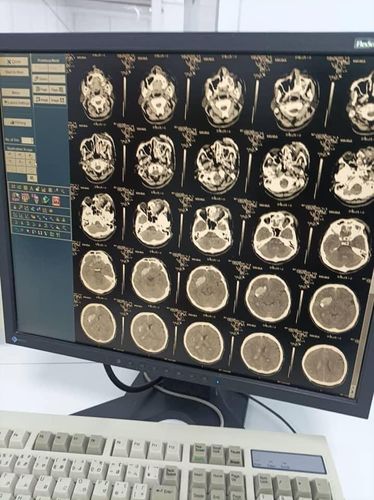

Neurosurgeons of the Jalal-Abad Regional Clinical Hospital performed an emergency complex brain surgery. Press center of the Ministry of Health of Kyrgyzstan reported.

The patient was admitted with an open penetrating wound to the head — the bullet was in the frontotemporal lobe on the right.